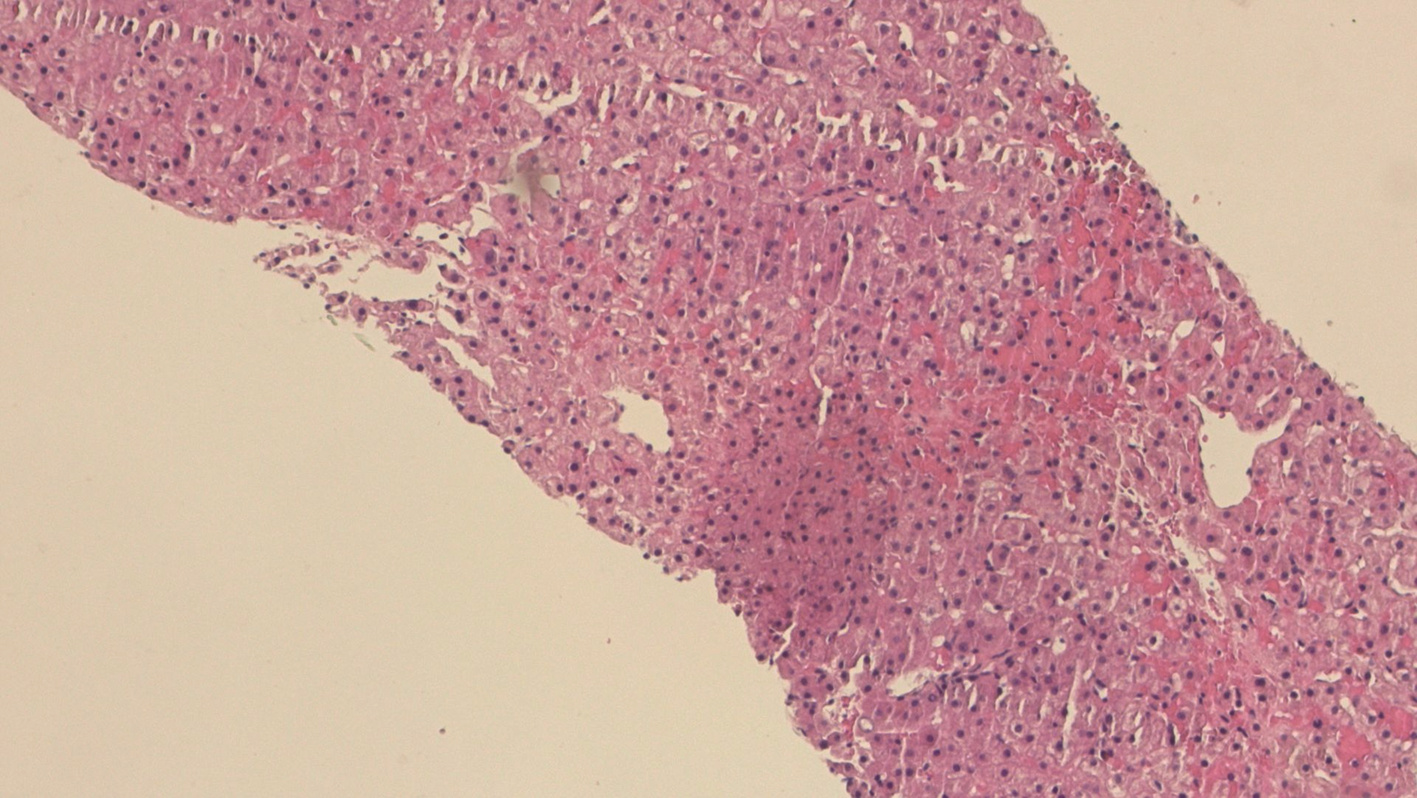

A diagnosis of atypical autoimmune hepatitis: A case report

Mengting ZHOU, Hongmei HAN

2022, 38(11): 2565-2567. DOI: 10.3969/j.issn.1001-5256.2022.11.024

Abstract(1112) HTML (309) PDF (2703KB)(99)